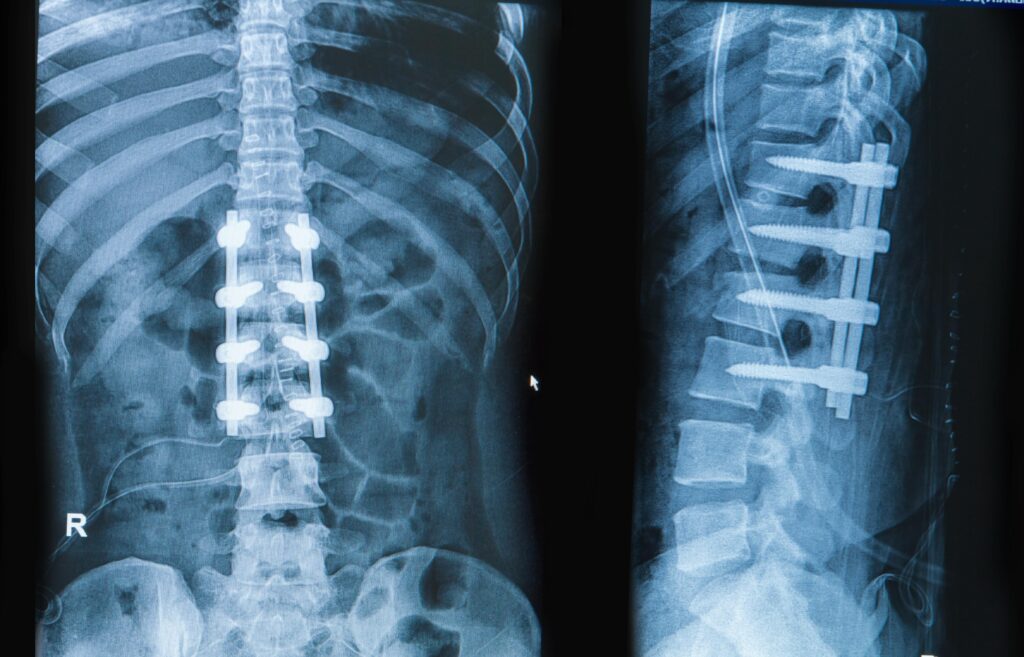

Cihazlar, omurgayı stabil tutarak iyileşme sürecini hızlandırabilir. Ciddi kırıklarda, özellikle omurga sinirlerini etkileyen veya omurganın stabilitesini bozan durumlarda cerrahi müdahale gerekir. Kırık olan omurganın düzeltilmesi için vida, çubuk veya plak kullanarak omurga stabil hale getirilir. Sinirlerin baskı altında olduğu durumlarda, sinirlerin rahatlaması için omurga kemiği çıkarılır. Füzyon ameliyatı, iki veya daha fazla omurganın kaynaştırılması işlemidir. Bu, kırıkların daha sağlam hale gelmesine yardımcı olur ve stabilite sağlar.